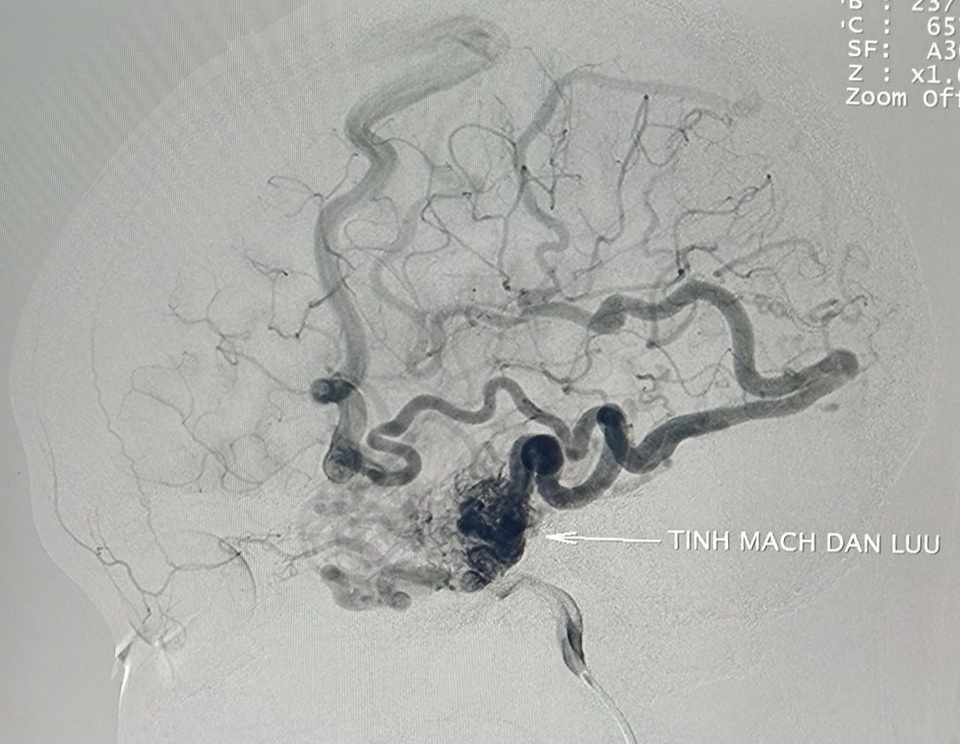

Qua thăm khám, chẩn đoán hình ảnh các bác sĩ phát hiện trên phim chụp mạch máu não xóa nền có khối dị dạng mạch máu não thái dương trái ở vị trí tĩnh mạch dẫn lưu. Búi dị dạng phình lớn, dọa vỡ bất kỳ lúc nào có thể cướp đi sinh mạng của người bệnh. Đây chính là nguyên nhân khiến cô gái trẻ thường xuyên rơi vào động kinh, đau đầu dữ dội.